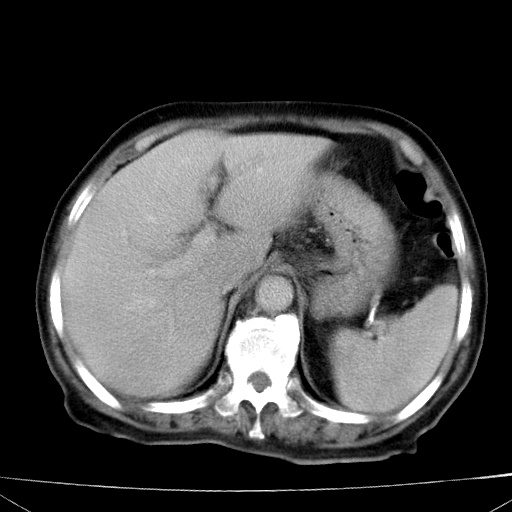

网站人气太旺!昨天的帖子就沉到海底,只好再发贴!ct18338:女 78岁,肝胆病变,已增强,再会诊!原帖链接:http://www.radida.com/bbs/forum.php?mod=viewthread&tid=50032

1)考虑胆囊癌侵犯肝脏并肝门区、腹膜后及右侧膈角后淋巴结转移。2)肝左叶近肝顶部囊肿。3)肝左叶肝内胆管结石。4)左肾近下极囊肿。